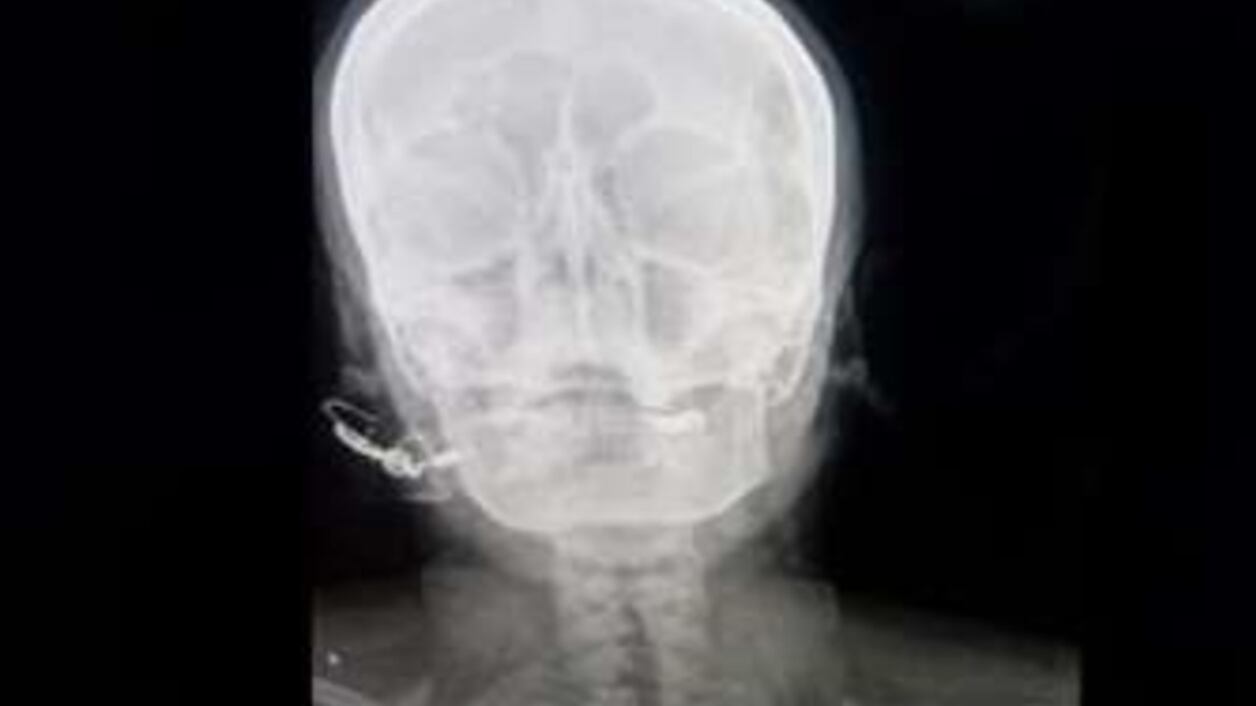

“Estaba totalmente consciente, pero sufría mucho”, indicó el galeno. Una radiografía confirmó que el clavo había sido introducido cinco centímetros en su cráneo, aunque no alcanzó el cerebro. La mujer, madre de tres hijas, afirmó estar embarazada de una cuarta.